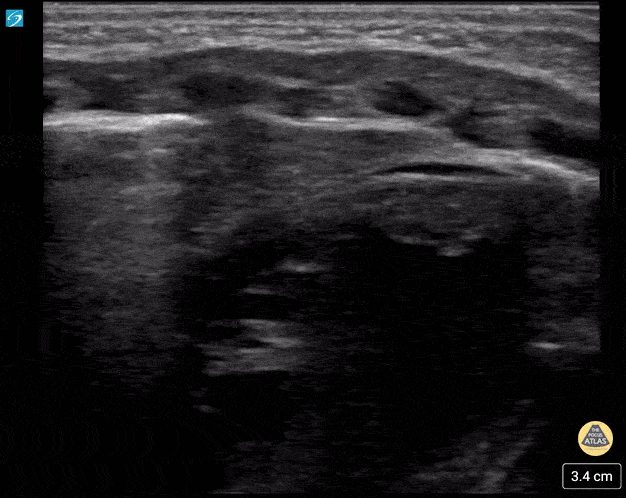

Thymus, 10 day old male. Contributors: Ana Ruiz-Castaneda, MD, Paul Khalil. MD